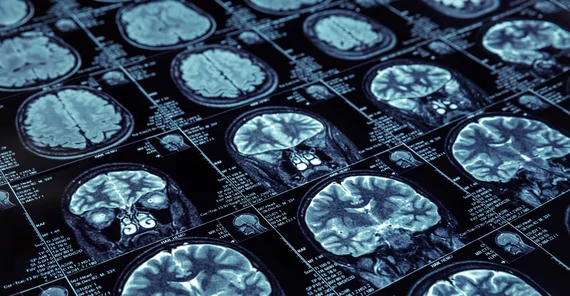

In addition to experiments on cognition and balance, the experimental part of the study includes EEGs and MRIs to find out more about what influences postural control in older people in particular. “The number of falls increases enormously in those over 65,” the psychologist explains. The risk of falling is particularly high when older people do several things at the same time, that is, while multitasking. “With advancing age, abilities deteriorate at varying rates. Maintaining balance, mobility, and coordination require more attention than in younger years.” At the same time, working memory – associated with the prefrontal cortex at the front of the brain and particularly important for flexible action control – is more cognitively challenged.

Berlin Center for Advanced Neuroimaging. Charité. A sunny 25°C. The last part of the study awaits me: In Berlin’s Charité Hospital I have to perform the tasks while in an MRI scanner. First, a staff member explains the procedure: I must not have any metal on or in my body, have to take off my shoes, and can press an emergency button if necessary. Claustrophobic people will certainly not feel well inside the scanner. I am not allowed to move my head –stabilized with two cushions – during the test. Above my head is a screen displaying the exercises. Stelzel and her colleague cannot hear me while I’m doing my tasks in the tomograph. Only during breaks can we communicate via an intercom. Because it’s very noisy inside the scanner, I’m given earplugs and sound-absorbing headphones. These are necessary, since my task is to recognize a “target sound” and a “target square” and confirm by pressing a button. Many sequences of the task follow, as I lie still in the scanner for 90 minutes. Outside again, my fingers are somewhat cold, my legs have fallen asleep, and my neck is a bit stiff. Otherwise I feel fine. As a farewell gift, I’m given an MRI scan of my brain.

“Functional MRI is a method that offers good spatial resolution,” Stelzel explains to me. “It shows oxygen consumption in the brain and, thus, activity changes in certain brain regions.” Specific regions demand a lot of oxygen during particularly difficult tasks. In contrast, EEG has a high temporal resolution and records electrical activity changes in milliseconds, so both methods are well suited to visualizing the difficulty of tasks. In addition, MRI indicates the connectivity between brain regions, thus making visible which regions cooperate during which tasks. The researchers ultimately hope to combine the two datasets for each test subject. It is conceivable that particularly difficult tasks lead to significant voltage swings (EEG) and high activity in certain brain regions (MRI) as well as more swaying on the force plate. Conclusions could, then, be drawn as to which cognitive tasks impair a person’s balance, and suitable forms of training (so-called “multitask balance training”) could be developed to ultimately reduce the risk of falling.